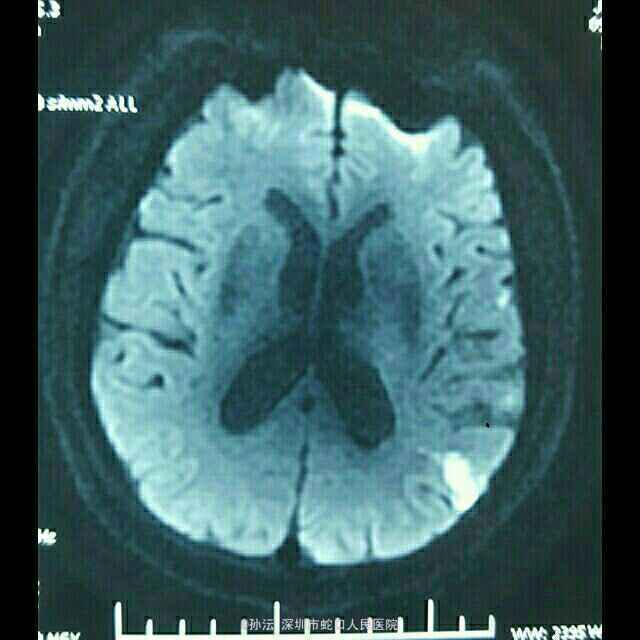

65岁男性,突发言语不利伴四肢乏力2天。 2天前无明显诱因突然言语不利,吐字不清,伴四肢乏力,以双下肢明显,表现为行走笨拙,伴肢体麻木,无头晕、头痛,无饮水呛咳、流涎,无意识不清、大小便失禁,无四肢抽搐。既往血压偏高5年,未使用降压药,血压未监测。

查体:BP 149/85mmHg,心肺听诊无异常。腹平软,无压痛、反跳痛,双下肢无水肿。神经系统检查:神志清楚,构音不清,记忆力、定向力、理解力、计算力均下降,两眼球活动自如,未见震颤,双瞳等大等圆,光反射灵敏,两侧额纹对称,右侧鼻唇沟浅,伸舌偏右,咽反射灵敏,颈软,四肢肌力5级,肌张力正常,腱反射对称,右侧病理征可疑阳性,共济征阴性,克氏征、布氏症阴性。NIHSS评分4分。 门诊头颅CT提示:脑萎缩。血液流变检测:全血粘度低切9.76mPa.s。糖化血红蛋白测定 HbA1c 6.60%。头颅MRI平扫(3.0T)示:左侧大脑分水岭区急性脑梗塞。脑小血管病变,FazekasⅡ级;轻度老年脑改变、部分空泡蝶鞍。

定位于左侧大脑中动脉及后动脉,定性动脉粥样硬化性血栓形成。 治疗上予依达拉奉清除自由基、奥拉西坦脑保护、血栓通改善微循环、阿司匹林抗血小板聚集、阿托伐他汀抗动脉硬化及对症治疗。